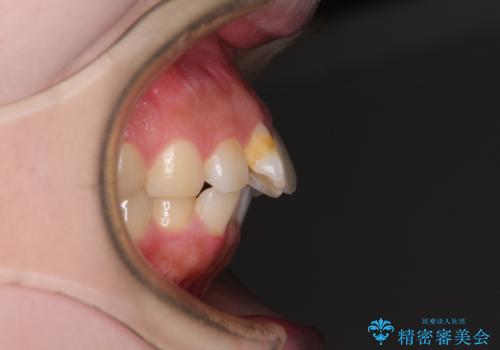

前歯のデコボコをインビザラインできれいに整える

- 前歯のデコボコと上下の隙間を気にして来院された患者様です。

前歯の捻れを改善するとともに、口元が少しでも引っ込むように治療計画を立て、仕上げることができました。